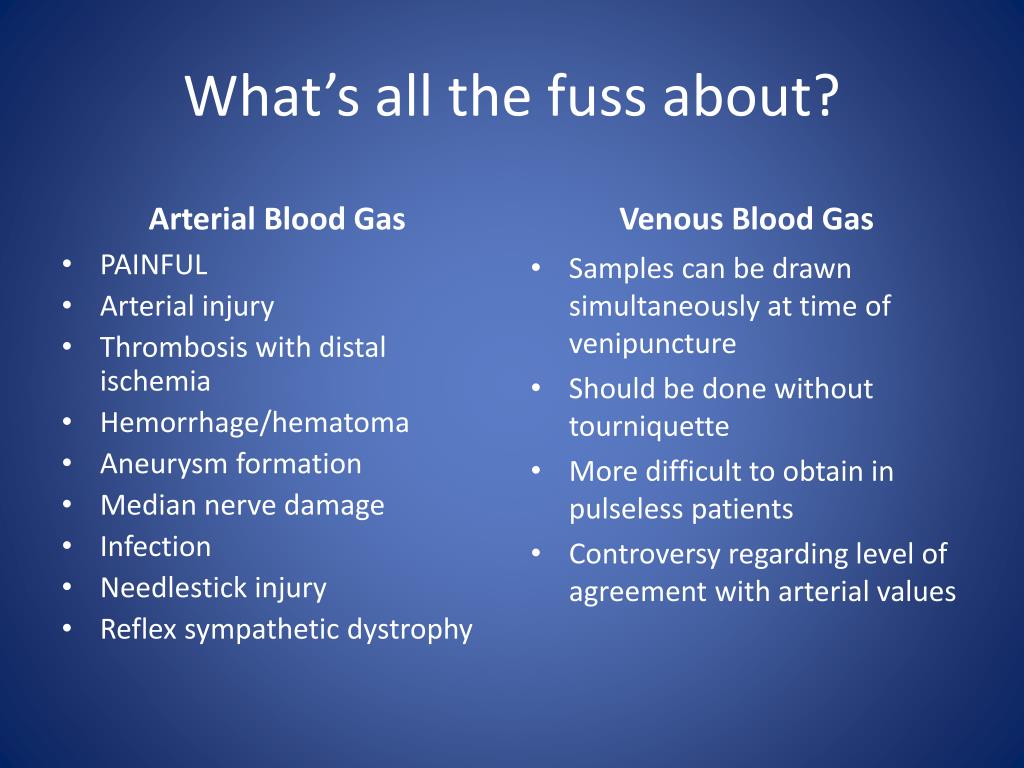

Arterial Blood Gases